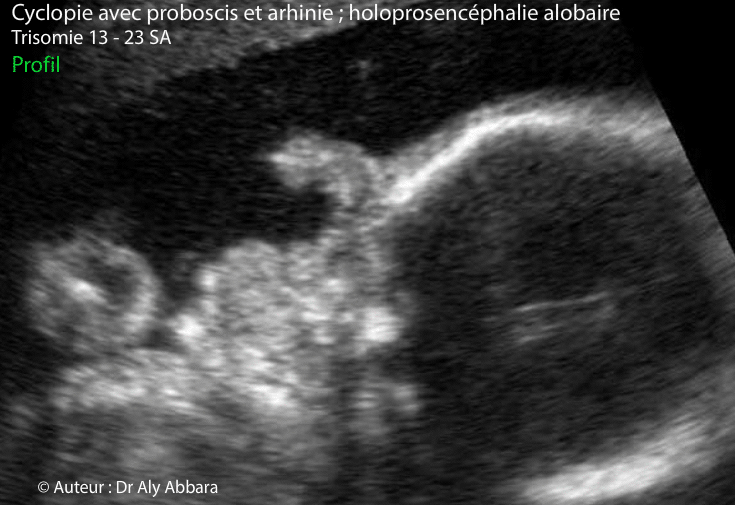

Images échographiques d'un profil fœtal présentant une cyclopie avec un proboscis et arhinie.

Les coupes axiales du même fœtus montrent la présence d'holoprosencéphalie alobaire avec hydrocéphalie majeure ; puis deux yeux fusionnant sur la ligne médiane pour former une seule masse oculaire (synophtalmie).

Les coupes frontales de la face montrent le proboscis, la monophtalmie avec deux yeux fusionnant ensemble, mais partiellement et enfin, une hypoplasie des processus frontaux du maxillaire avec absence de cavité nasale.

Dans le cas présenté dans cet article, le fœtus est trisomique 13 âgé de 23 SA.

L'étude de la morphologie révèle la présence d'autres anomalies en dehors de la séquence holoprosencéphalie alobaire avec microcéphalie (périmètre céphalique = 170 mm, soit "-3,24 DS") : une hypoplasie du pavillon de l'oreille externe ; un spina bifida aperta ; un spot blanc intracardiaque ; une hyperéchogénicité intestinale ; une artère ombilicale unique ; main crispée unilatérale et enfin, un retard de croissance in utero modéré et symétrique.